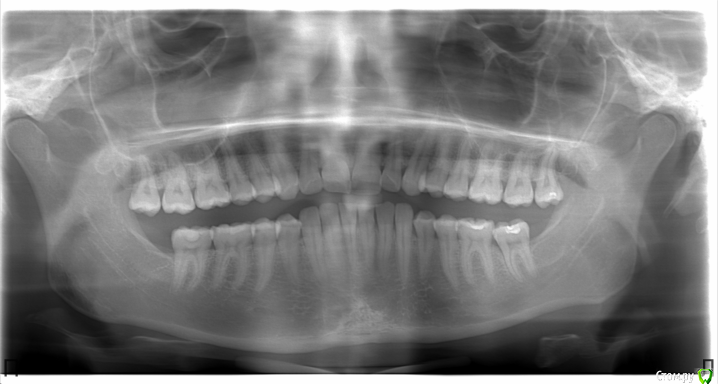

aleksandrovna_o Опубликовано 18 ноября, 2015 Поделиться Опубликовано 18 ноября, 2015 Здравствуйте.Мне 26 лет, дистальный глубокий прикус, на ВЧ скученность зубов. Все зубы свои, удалены 8-е на нижней челюсти.3 ортодонта сказали,что нужно удалять 4-ки, если их не удалить, то увеличится сагиттальная щель, челюсть ещё больше выдвинется вперёд, изменится профиль.4-е зубы не хочу удалять. Возможно ли в моей ситуации удалить 8-е на ВЧ и (или) сделать сепарацию, чтобы освободить место. Мне даже не нужно, чтобы зубы идеально встали в один ряд, просто хоть чуть-чуть исправить?Очень боюсь, что черты лица изменятся (впалые щёки, выраженные скулы). Очень рассчитываю на Ваш ответ. Снимки прилагаю. Ссылка на комментарий

Caries Опубликовано 26 ноября, 2015 Поделиться Опубликовано 26 ноября, 2015 Удалить восьмые на вч, два микроимплантата на их место через полгода, дистализация моляров. При грамотном подходе профиль изменится в любом случае.Наклон резцов вч нужно исправлять Ссылка на комментарий